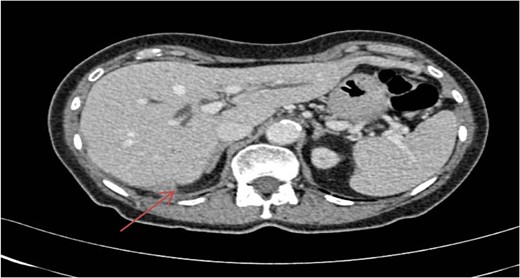

CT scan of abdomen showing soft tissue mass posterior to liver.

Her symptoms had been managed conservatively until re-presenting 3 years later with a back (lumbar) lump. Due to the uncertainty over the nature of this back lump, a CT and magnetic resonance image (MRI) of the abdomen was carried out. This revealed an abnormal 6.2 × 3.1 × 11.4 cm3 retroperitoneal collection extending from the posterior right edge of the liver until passing through the abdominal wall to form the palpable mass in the right flank (Figs 1 and 2).